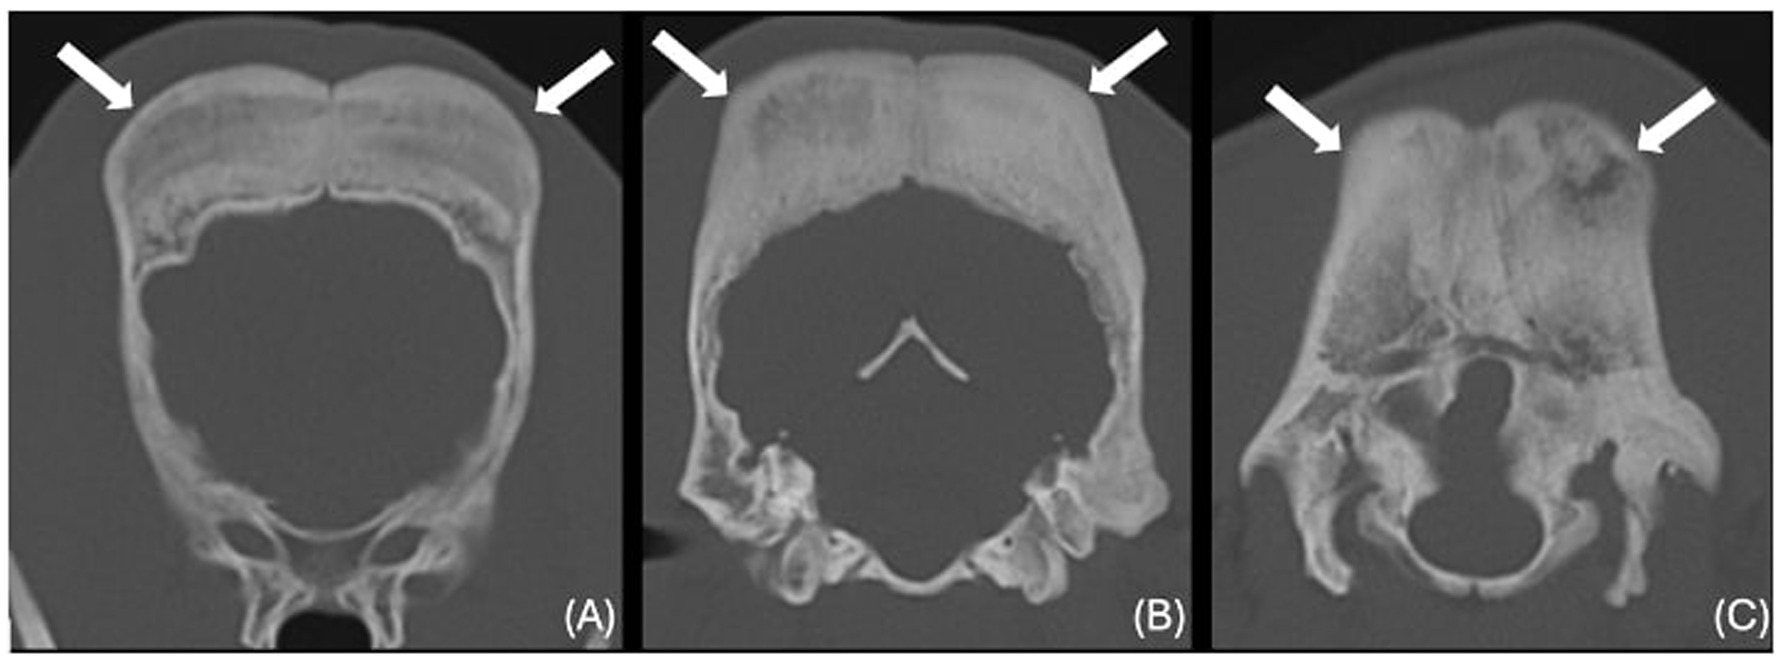

The images revealed severe, bilateral and symmetrical thickening of the parietal, occipital and frontal bones, as well as the squamous part of the left temporal bone (Figure 1, white arrows). The lesions were characterised by prominent bone sclerosis, which appeared lamellated in some areas, as well as more focal irregular areas of hypoattenuation with punctate lysis of the cortex (at the right frontal, left parietal, and left occipital bones) (Figure 2, white arrowheads). The osteopenic areas were occupied by mixed soft tissue and fluid attenuation with patchy contrast enhancement (Figure 3, black arrows). Irregular margination with smooth periosteal reaction of the intracranial side of the occipital and parietal bones was also noted. The os tentorium was thickened and sclerotic, especially on the left side.

Figure 1. Transverse CT images of the frontal (A), parietal (B) and occipital bones (C) (window level 300HU, widow width 1500HU) unenhanced, showing severe thickening and sclerosis (white arrows).